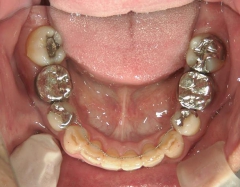

矯正歯科 治療後矯正歯科 全顎ワイヤー矯正 治療後矯正歯科(全顎ワイヤー矯正)治療後

矯正歯科 治療後 左上6番欠損のため、7番を6番の位置へ前方牽引

矯正_灰色.pngno.22_8175_治療後_下.jpg矯正_灰色.png